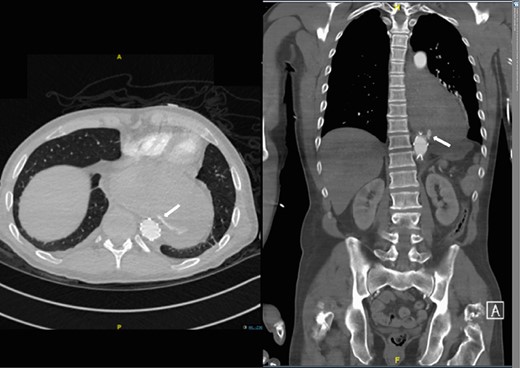

A 57-year-old male presented haemodynamically unstable with a blood pressure of 85/50 mmHg and a heart rate of 136 bpm with haematemesis, melaena and 4-day history of back pain. Fifteen years previously he was treated for a poorly differentiated adenocarcinoma (pT3 pN1 MX) close to the gastro-oesophageal junction with chemotherapy and trans-hiatal oesophagectomy. He received no radiotherapy. Apart from being a life-long smoker he had no other positive social risk factors or medical history. He underwent immediate oesophago-gastro-duodenoscopy (OGD). This showed fresh and clotted blood in the gastric remnant but no bleeding source was identified. He had a pulseless arrest during the OGD but underwent successful cardiopulmonary resuscitation. Following this a CT angiogram was performed. This demonstrated a fistula between the neo-oesphagus and the thoracic aorta (Fig. 1). Following discussion between an upper gastro-intestinal surgeon, a vascular surgeon and an interventional radiologist the patient was taken to the operating theatre. Under general anaesthesia an initial thoracic aortogram was performed from the right groin to confirm the presence and location of the AGF (Fig. 2). Following this, a covered thoracic stent graft (Cook Medical ZTA-24-105/diameter of 24 mm and length of 105 mm), was inserted via the femoral artery under image guidance. The stent graft, usually used in aneurysmal repair, was placed in the thoracic aorta across the fistula and occluded it. Subsequent angiogram showed no leak (Fig. 3). The patient became haemodynamically stable and had an uneventful recovery.

CT angiogram showing aorta-enteric fistula demonstrated by arrow (axial and sagittal view, respectively).